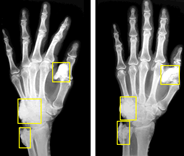

Hand bone age AI

Predict hand bone age. In a small test of 129 random Stanford clinical cases, AI predicted age within 12 months.

C. Fang, S. Baig, D. Larson, M. Fadell, B. Do